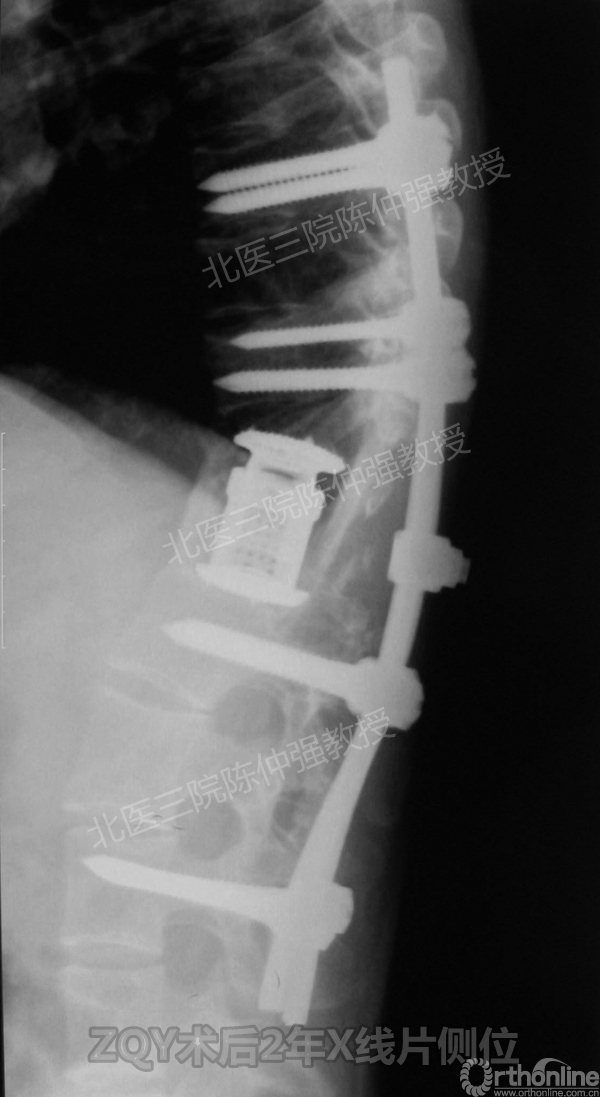

ZQY术后2年

患者女性17岁,胸腰椎陈旧结核性侧后凸畸形,局部呈“麻花状”扭转,无神经功能受损表现。2005年,陈仲强教授带领团队实施后路+侧前方联合入路脊柱节段切除、双轴旋转矫形术。术后患者外观显著改善,神经功能正常。术后随访证实患者截骨矫形节段骨性融合良好,矫形效果持续良好。